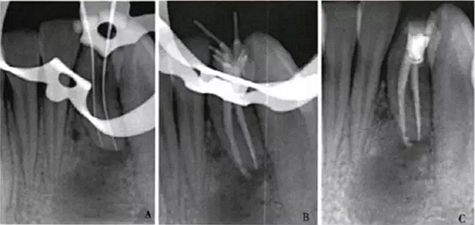

1周后,患者述疼痛消失。復(fù)診采用冷測壓方法根管充填(圖2),牙冠開髓孔處應(yīng)用Chem—flex(DentsplyDeTreyGmbH,Konstanz,Germany)充填。由于患牙牙冠形態(tài)異常,且唇側(cè)形態(tài)尚未恢復(fù);患牙周圍有牙石、軟垢,建議患者行牙周及修復(fù)治療以維持長期療效,被患者拒絕。9個月后隨訪,患者自述患牙經(jīng)治療后無癥狀,臨床檢查見32叩診正常,無松動;影像學(xué)檢查見32根尖周圍透射區(qū)域明顯減?。▓D3)。

A:32術(shù)中片確定根管工作長度;B、C:32術(shù)后片示根管充填適充

圖2 32根管治療x線片